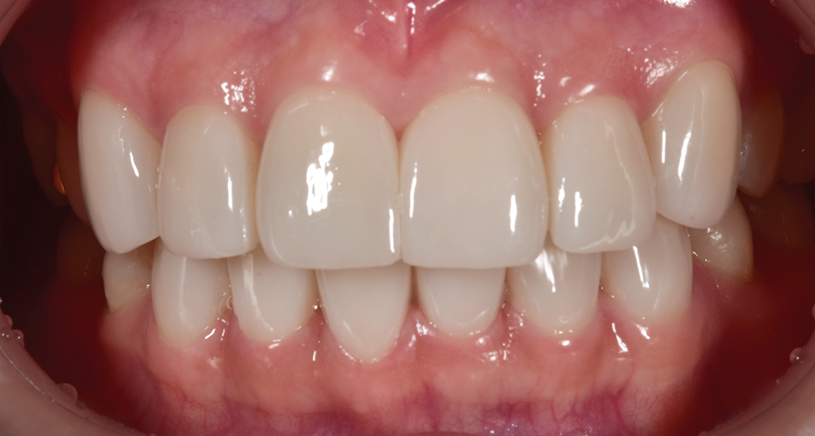

< 사례 1 >

블랙트라이앵글 무삭제라미네이트 <블랙필름> 치료 전

블랙트라이앵글 무삭제라미네이트 <블랙필름> 치료 후